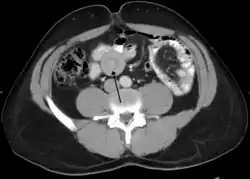

| An intussusception as seen on CT | |